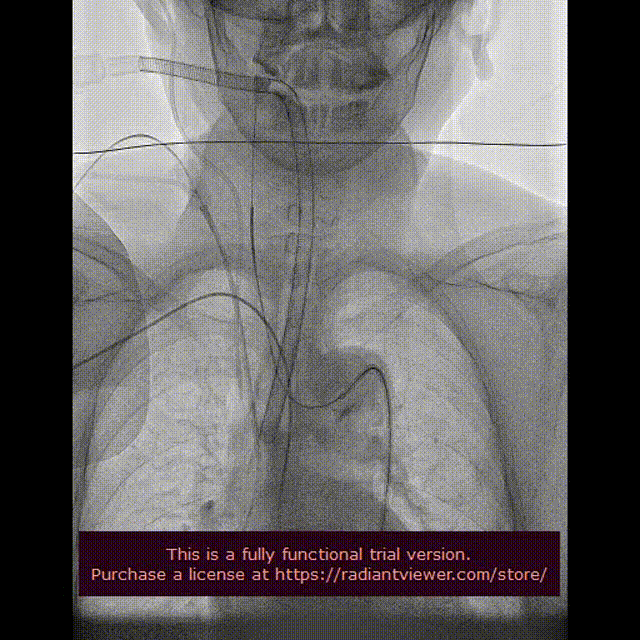

在神经内科方朴主任以及放射科,超声科和麻醉科等科室的通力协作下,顺利完成了术前准备,术者团队在术中谨慎建立轨道,根据主动脉根部造影的结果选择合适的跨瓣体位。

右颈置入保护伞

左颈置入保护伞